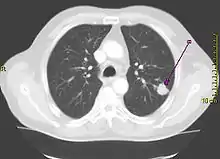

Représentation en coupe tridimensionnelle par tomodensitométrie d'un poumon présentant une tumeur.

Scanner montrant une tumeur cancéreuse dans le lobe supérieur du poumon gauche.